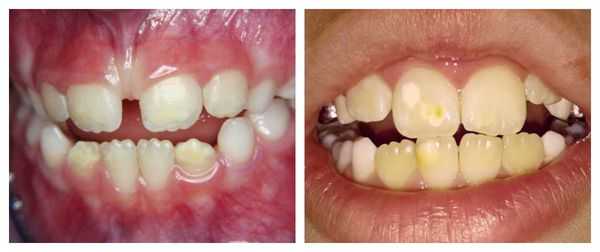

Отдельно рассматривают формы системной гипоплазии, которые затрагивают дентин:

- Зубы Гетчинсона — аномалия, при которой коронки центральных верхних резцов имеют отвёрткообразную форму с полулунными вырезками по режущим краям [9] .

- Зубы Фурнье — зубы бочковидной формы без полулунной вырезки, шейки которых больше режущих краёв.

- Зубы Пфлюгера — аномалия первых моляров (жевательных зубов). Возникает в результате сифилитической инфекции [7] . Зубы имеют конусовидную форму, их бугры недоразвиты, шейки больше жевательной поверхности.

- Зубы Гетчинсона. При данной патологии верхние центральные резцы имеют отверткообразную или бочкообразную форму. Их размер у шейки несколько больше, чем у режущей поверхности и имеется полулунная выемка у режущего края. Ранее полагалось, что данный симптом наблюдается только при врожденном сифилисе, однако позже установили, что аномалия возникает и при иных причинах.

- Зубы Пфлюгера. При данном симптоме поражены первые моляры, размер коронки у щеки больше, чем у жевательной поверхности. Бугры недоразвиты, что придает зубам схожесть с конусом.

- Зубы Фурнье. Клинически выглядят так же, как и при симптоме Гетчисона, но без полулунной выемки.